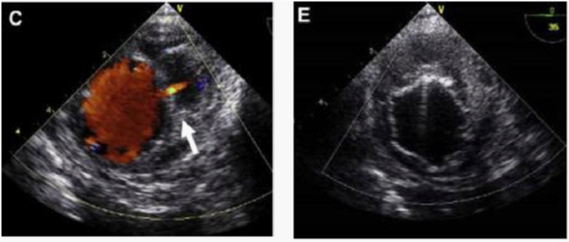

In contrast, Echo Doppler has been recognized as a good option to these techniques due to its low cost, easy implementation and interpretation and the absence of exposure to any type of radiation.26 This provides a better understanding of the endoleak formation mechanism and provides a more accurate analysis thereof, due to a collateral circulation. The origins of an endoleak may also be correctly identified. Compounded by the fact that it allows visualize blood flow in the aneurysm sac and its direction. This seems to be an excellent tool in the evaluation of high flow endoleaks within the aneurysmal sac. It is an imaging technique commonly used in vascular studies, being easy to perform, inexpensive, portable, secure and highly available. Its use for patients’ follow-up can reduce the biological hazards associated with CT angiography, since this frees the body of the individual to a substantial dose of ionizing radiation. The advantage of Doppler ultrasound in patients’ follow-up with aortic stent graft is that it allows a serial measurement over time of the residual diameter of the aorticaneurysm sac. Doppler ultrasound is more accurate than CT for the detection of problems associated with stent graft patency, their migration, kinking and stenosis. Provides physiological and anatomical information at the same time, unlike CT. The ability to quantify and compare serial images at a low cost without contrast and radiation, suggests that this technique should be the Gold Standard in the follow-up to TEVAR (Figures 5-9).20,24,27

Figure 9 (C) Image showing active bleeding from the aortic lumen into the hematoma (arrow). (E) TEVAR showing elimination of flow.30